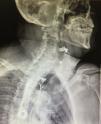

The variables studied were age, sex, indication for surgery (benign or malignant disease), comorbidities, clinical stage in the cases of malignant lesions, neoadjuvant therapy, surgical technique, type of reconstruction, complications, surgery duration, blood loss, preoperative and postoperative hemoglobin levels, anastomotic leak, and leak detection through contrast-enhanced swallow study. Said contrast-enhanced study was carried out between 5 and 7 days after surgery with water-soluble material. Anastomotic leak was defined as the leakage of contrast material from the esophageal lumen reported by the radiology service (fig. 1). Clinical anastomotic leak was defined as the leakage of saliva or food through the surgical wound in the neck or the presence of an abscess at said level that required the opening of the surgical wound (fig. 2).

All 30 patients with anastomotic leak underwent contrast-enhanced swallow study at a mean 8.96 postoperative days (5-30 days), with a median of 7 days. However, the contrast-enhanced study was negative in 17 of those 30 patients, resulting in a sensitivity of 43.33% for the detection of leaks through the contrast-enhanced swallow study.

We reported that 42.85% (n = 30) of our study patients presented with anastomotic leak after esophagectomy and that all of them (100%) underwent the contrast-enhanced swallow study. Said study detected the leak in only 17 patients, signifying sensitivity of 43.3%, a low and obsolete percentage for early leak detection. Consequently, the leaks in a high number of patients were not opportunely detected, increasing the risk for complications.